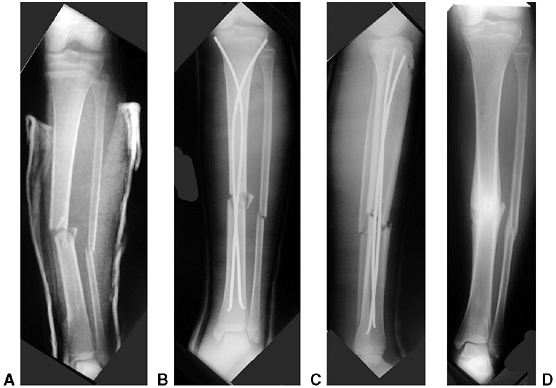

![]() |

Figure 33.16 A:

The typical orientation of the fracture line in the supracondylar fracture. Sagittal rotation of the distal fragment generally results in posterior angulation, although, less commonly, it can be flexed. B: The cross-sectional area through the fracture demonstrates the thin cross-sectional area of the supracondylar region. C: Any horizontal rotation tilts the distal fragment. Typically, medial tilting occurs, producing cubitus varus. The lateral projection readily demonstrates this horizontal rotation, producing a fishtail deformity. In this instance, the distal portion of the proximal fragment is obliquely profiled, although there is a true lateral view of the distal humeral fragment. |